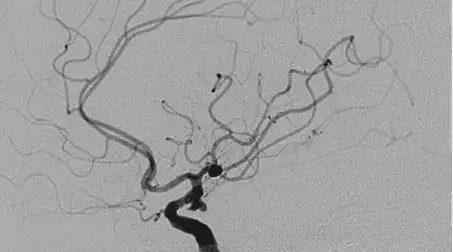

此外,Wolterink等利用CT冠状动脉动脉造影自动定量评价冠状动脉积分,该研究纳入了250例同时接受了冠脉CTA及心脏钙化积分(cardiac calcium scoring CT,CSCT)扫描的患者,采用配对卷积神经网络识别CT冠脉动脉造影钙化积分。与CSCT结果相比,钙化斑块的质量积分一致性为0.944,且83%患者的Agatston积分风险评估一致。提示CT冠脉造影能准确、定量评价钙化斑块积分,有望在将来减少不必要辐射剂量。

Zreik等利用深度学习方法自动识别患者冠脉CT血管造影(coronary computed tomography angiography,CCTA)图像中局部心肌异常,从而推断出支配该区域的冠状动脉病变。该研究纳入了166例同时接受了侵入性血流储备分数(fractional flow reserve,FFR)检查及静息状态下CCTA扫描的患者。

研究首先利用多尺度卷积神经网络对患者CCTA图像中的左心室心肌进行整体分割,然后将左室心肌进一步分成许多有着空间连接关系的簇,并利用无监督自动编码统计数据计算提取每簇心肌的特征;接下来根据提取出的特征使用SVM分类器对这些心肌进行分类,从而判断患者是否有冠状动脉功能性狭窄。

该研究分别使用了20张CCTA图像训练左室心肌的分割及左室心肌自动编码器,结果显示20张图像中左室心肌分割的定量评估Dice系数平均为0.91;接下来进行10折交叉验证试验,在剩余的126个CCTA扫描中进行患者分类,其诊断的AUC值为0.74±0.02。该研究结果表明,AI在未观察患者冠脉解剖结构的情况下,通过静息CCTA图像中心肌的自动分析即可判断冠状动脉的功能性狭窄,将来有望减少不必要的侵入性FFR检查。